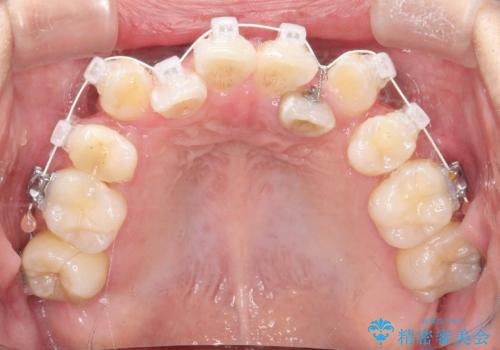

【ワイヤー矯正】八重歯 歯のでこぼこを治したい!

- 治療計画

- 「歯のでこぼこを治したい」を主訴に来院された患者様です。 上下ともに、歯のでこぼこが強く、上下左右4の抜歯をし、ワイヤー矯正で治療を行いました。

かなり綺麗に並ぶ事ができ大変満足していただけました。